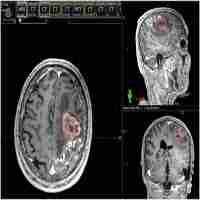

| Abstract | Maximizing the extent of tumor removal and preserving maximal neurological function are always the fundamental objectives in brain tumor surgery. This has motivated neurosurgeons to try various ways to map brain functions before tumor resection. Navigated transcranial magnetic stimulation (nTMS) is a new noninvasive method for brain mapping, which has produced exceptional results in clinical practice in recent years. However, there are still many deficiencies which need to be addressed to make nTMS more suitable for clinical application and neuroscience research. In this review, we highlight the opportunities provided by nTMS mapping, analyze the shortcomings at a theoretical level, and then emphasize the possibilities and prospects of applying multimodal fusion nTMS. |